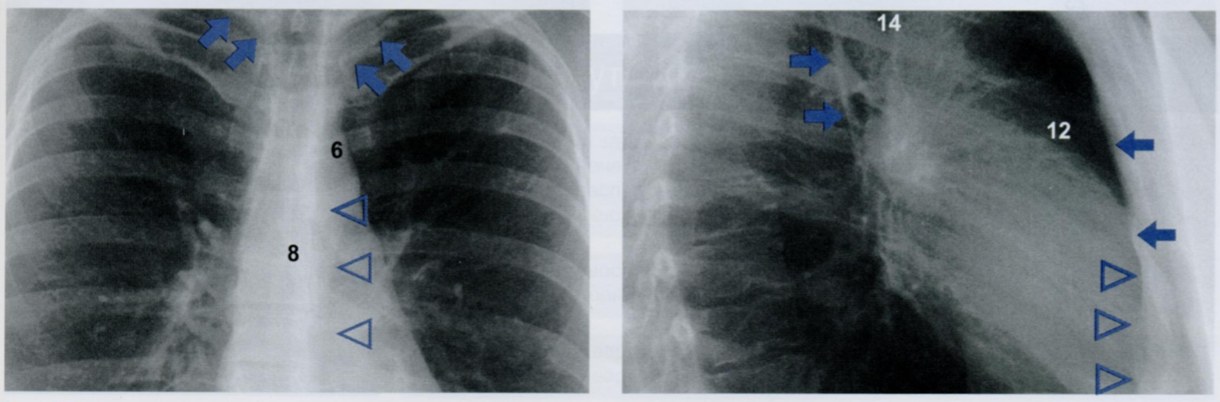

На первом снимке затенение выше ключицы (косые стрелки) образовано складкой кожи над ключицей (23), поскольку складка расположена по касательной к направлению рентгеновского излучения. Эта тень не имеет никакого отношения к плевре. Чем больше глубина надключичной ямки, тем лучше видна эта тень.

На втором снимке определяется вертикальная линия на уровне купола правого легкого. Это нормальное рентгеновское изображение грудино-ключично-сосцевидной мышцы, край которой расположен по касательной к ходу рентгеновского излучения.

Будьте внимательны, чтобы не принять тень, сопровождающую ключицу, или вертикальную тень от грудино-ключично-сосцевидной мышцы за тень плевры.